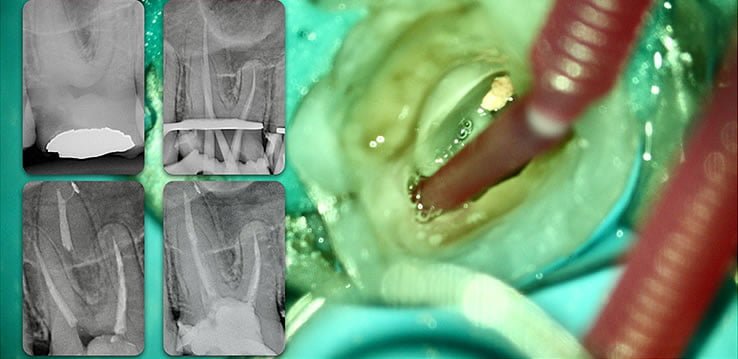

Template for x-rays

Biolight® DRILL-FREE posts are available in bundles of 4, 6, 9 and 12 strands. The post size is selected based on the width of the canal at the coronal area. Depending upon the canal width at the apical stop, a certain number of strands must be pushed to the stop. Both of the measurements are made with the assistance of a radiograph and the template that is included in the TRAINING KIT.